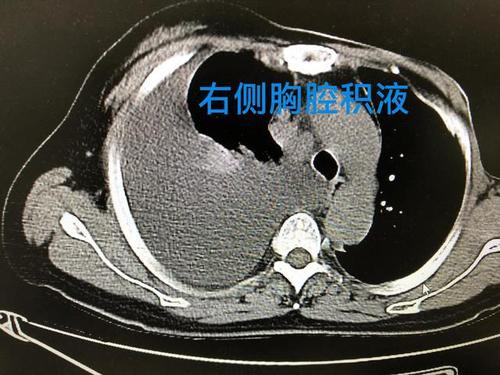

5月28日胸部ct可见右侧大量胸腔积液及左肺感染灶.